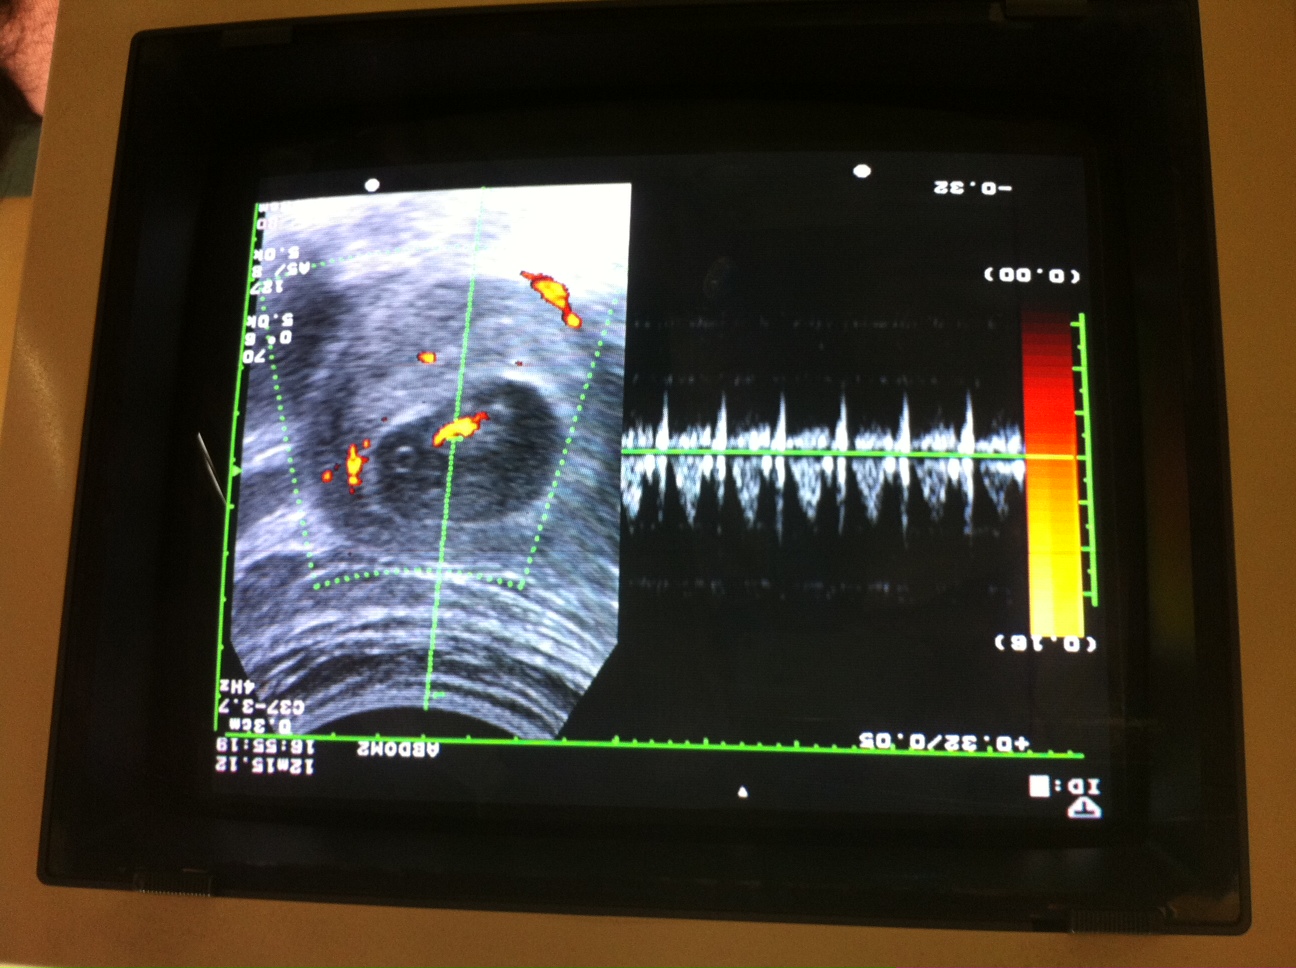

博元婦產科48歲試管嬰兒成功:(1)雙胞胎 (2)單胞胎 age 48 https://www.youtube.com/watch?v=SbBCmUObJnY

博元婦產科不孕症試管嬰兒中心蔡鋒博,陳昭雯醫師